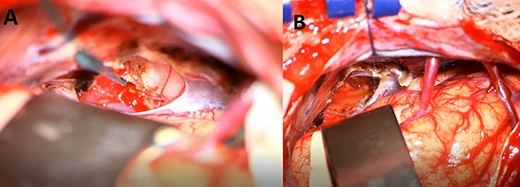

A 33-year-old lady presented to the clinic for bilateral retro-orbital headache with tinnitus most severe upon waking up in the morning for 3 months, without evidence of nausea, vomiting, or insomnia. Vital signs were within the normal range. The neurologic exam was non-focal. Enhanced brain magnetic resonance imaging (MRI) revealed a T1 hypointense, T2 hyperintense, homogenously enhancing Pineal tumor of 2 × 1.89 × 1.61 cm (anteroposterior × transverse × height) compressing the posterior wall of the third ventricle with evidence of moderate hydrocephalus (Fig. 1). The patient was scheduled for craniotomy for resection of the mass. In the operating room, an external ventricular drain was inserted in the right occipital horn followed by craniotomy and resection of the mass through a right occipital transtentorial approach. Gross total surgical resection was achieved under microscopic navigation (Fig. 2). The patient was extubated. Upon extubation the patient started to have chewing-like movement of her lips on the ET tube, afterward, she was transferred to the intensive care unit for monitoring. On postoperative day 1, we noticed that the patient was still having chewing-like movements typical of orofacial dyskinesia with evidence of buccal mucosal injury and swelling of the lips (Video 1). She was also complaining of inability to sleep. The patient was on regular postoperative medications (esomeprazole, cefazolin, paracetamol, morphine, dexamethasone, levetiracetam). An enhanced postoperative brain MRI was done for evaluation and confirmed complete resection of the lesion without any bleeding or ischemic changes (Fig. 3). The chewing like movements lasted for 72 hours and spontaneously resolved afterward. Pathology confirmed pineal parenchymal tumor of intermediate differentiation (WHO Grade III). The patient was treated with adjuvant radiotherapy. This is an unreported complication post pineal gland tumor resection in humans. Below we review the literature reporting abnormal facial movements associated with various pineal gland conditions as the data remains scarce concerning dyskinesia post pineal tumors resection in humans.

A postoperative day 1 T1 enhanced axial (A) and sagittal (B) MRI confirming complete surgical resection of the pineal tumor.